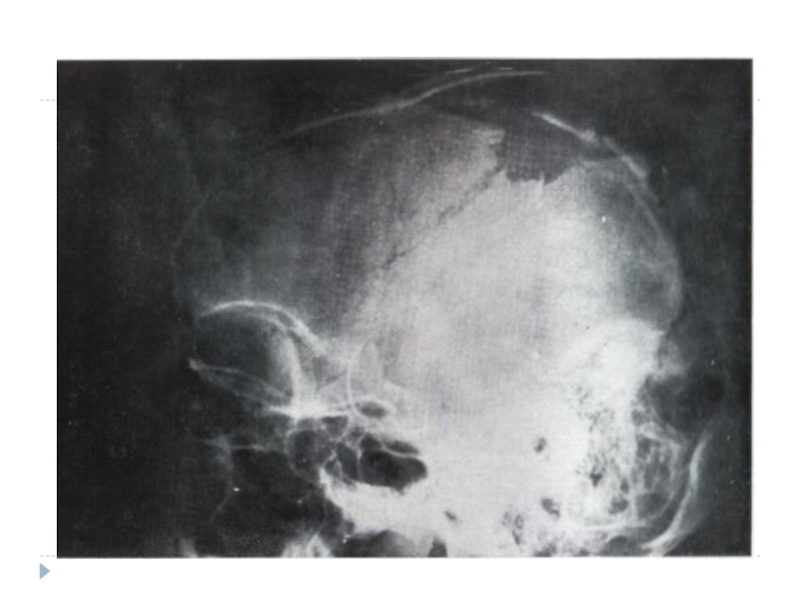

Слайд 7Диагностика

Производится рентгенография черепа, первичная хирургическая обработка (иссекают нежизнеспособные ткани, при вдавленном

переломе костей черепа через образованное фрезевое отверстие леватором поднимают вдавленный фрагмент).

При наличии многооскольчатого перелома удаляют свободно лежащие отломки кости, расширяют дефект, осматривают твердую мозговую оболочку. Она вскрывается при наличии гематомы.